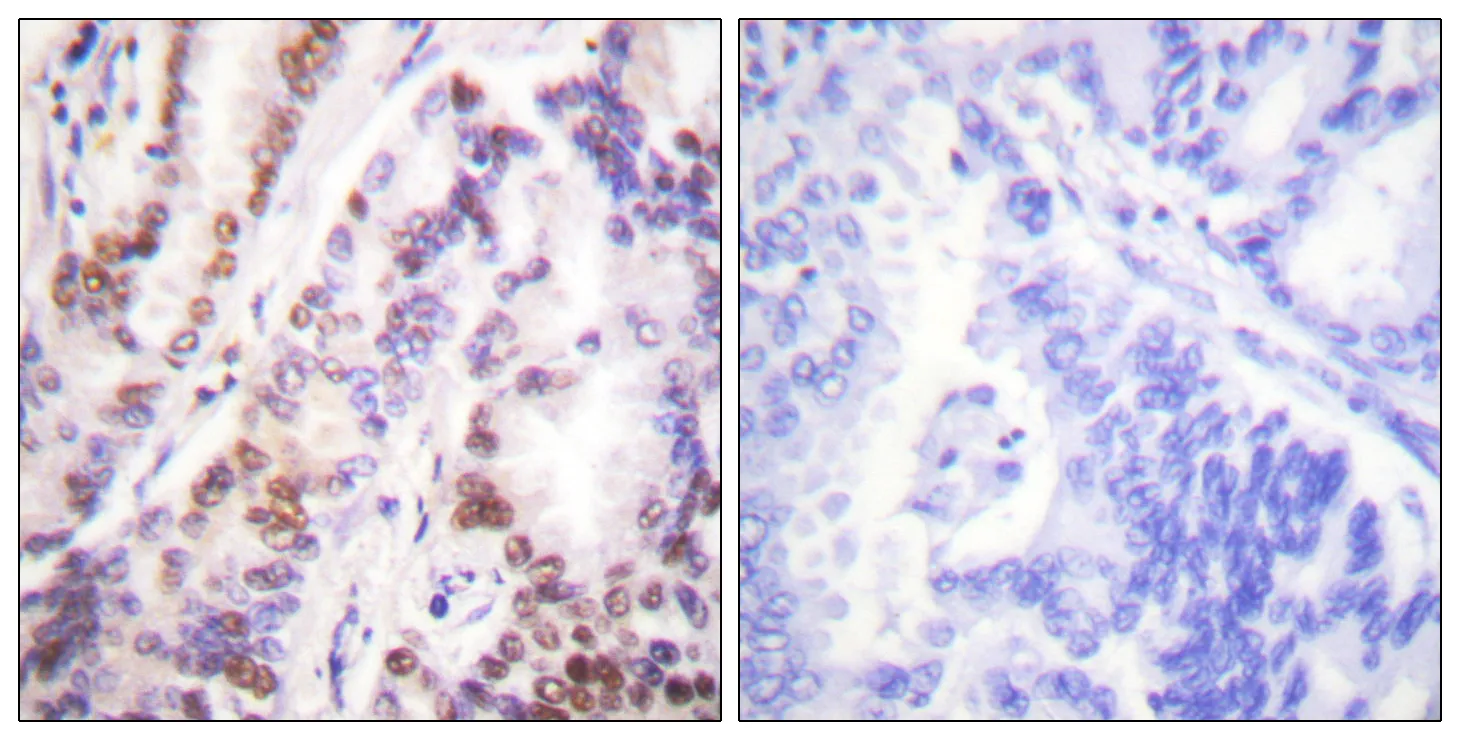

Histone deacetylase 9 Rabbit Polyclonal Antibody

Cat: APRab12050